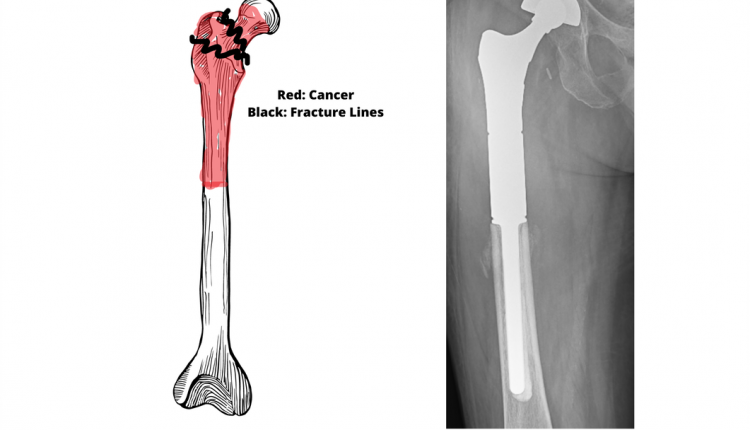

A team of ortho-oncologists removed cancer-affected broken bone from the ball of the hip joint up to the mid-thigh, measuring 17 cm long as a single piece.

The Limb Salvage Surgery was performed under the supervision of Dr. Srimanth BS, lead consultant Orthopaedic Oncology services, Apollo Cancer Centre, Bangalore, along with a dedicated team to get the best results from the surgery. The surgery lasted for three hours wherein in the first stage; the team of doctors removed the 17 cm long broken bone as a single piece (preventing tumor spillage by fixing it with a wire around the tumor). The second stage was to perform a tumor bipolar mega prosthesis replacement surgery.

The doctors performed a tumor mega prosthesis replacement surgery to preserve the limb.